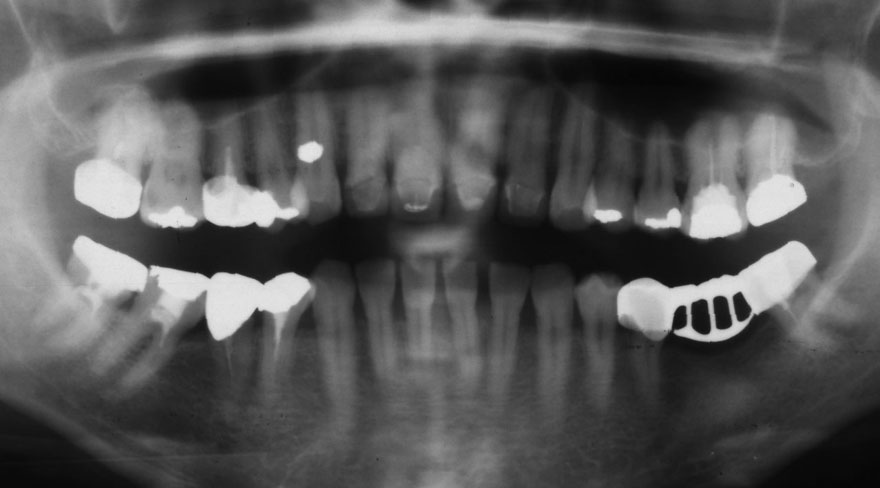

初診時 36歳 女性 平均歯槽骨喪失量:2.70mm

30年後 66歳

平均歯槽骨喪失量:3.26mm

30年間喪失量:-0.55mm

年間喪失速度:-0.018mm

(ケア頻度:3.01ヵ月ごと)